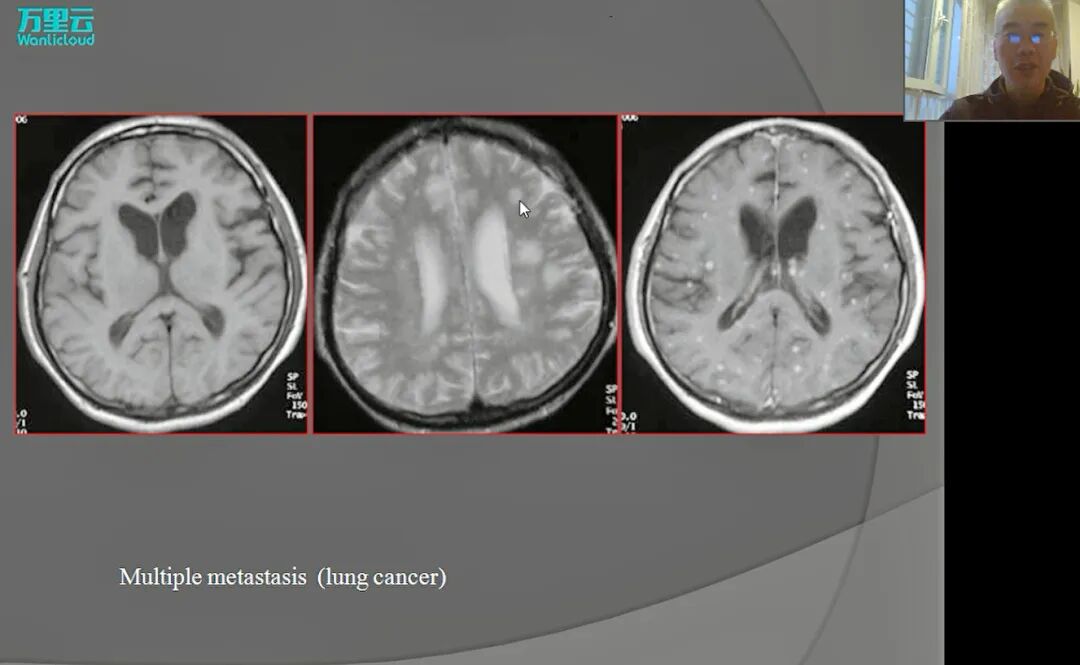

✔ 转移性肿瘤,约占颅内肿瘤分类的30%,常见于40至70岁人群,男性患有此肿瘤的概率高于女性(不含特殊病例)。值得关注的是,50%肺癌是此类肿瘤的原发性肿瘤。